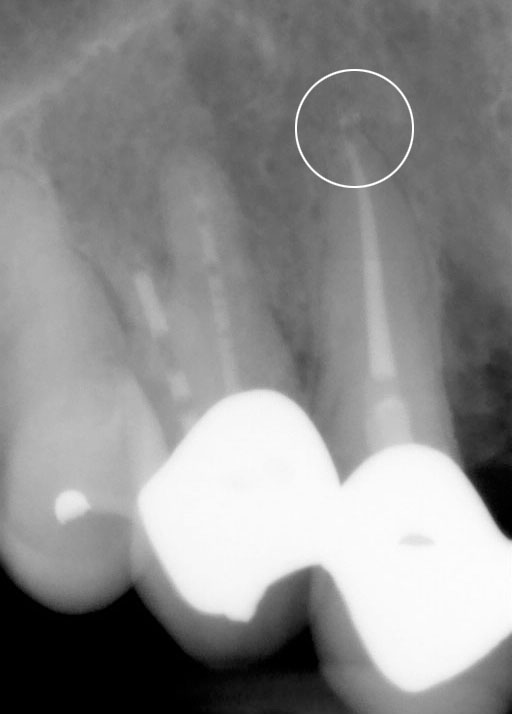

Op de tweede foto ziet u dezelfde kies net na de behandeling. Het kanaal is volledig schoon gemaakt en solide gevuld. Op de derde foto ziet u weer dezelfde kies een jaar na behandeling. De punt van de wortel laat geen zwarting meer zien en is volledig genezen.